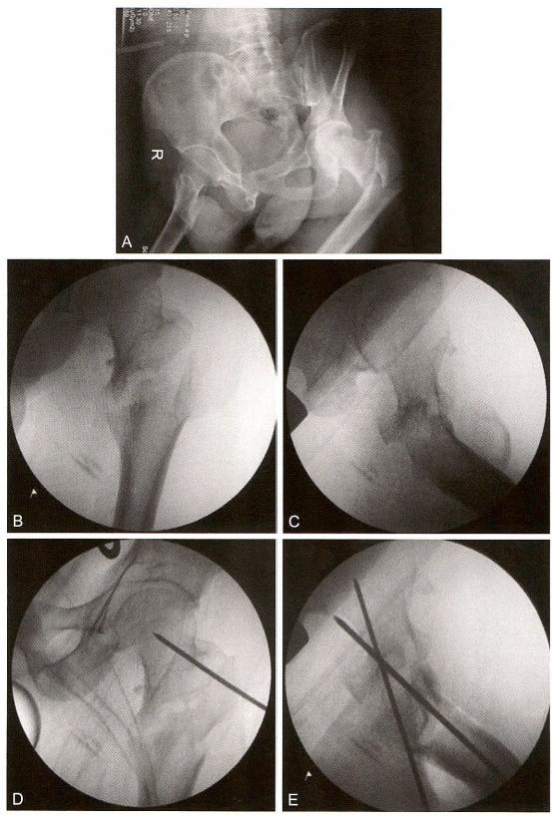

3)术中复位技巧3:点状复位钳钳夹固定(冠状位股骨转子间骨折)。 股骨大转子骨折线从前上方向后下方延伸,臀中肌的大部分位于近断端,臀中肌的前份在大转子的止点位于远断端,后方软组织铰链破裂,呈现骨折端后方张口,股骨颈及相连的大转子大部呈现极度外旋(图 9-10A 、B 、C)。先将远端外旋牵引,同时用点状复位钳钳夹,使骨折后方张口复位,然后经大转子后方植入克氏针,改内旋、内收牵引,在大转子顶点插入 导针,常规开口扩髓,植入主钉和螺旋刀片(图9-10)。

4)术中复位技巧4:对于难复型病例,可以综合运用多种方法复位, 此类简单骨折(AO 分型A1.2, 即2007版的A1.3) 复位非常困难。往往 由于复位不良,导致手术失败(图9-11A 、B); 牵引后正位复位不良, 近端矢状位旋前(图9-11C); 牵引后侧位复位不良,近端向前移位(图 9-11D) 。用点状复位钳钳夹复位,正、侧位良好,并用克氏针临时固定, 然后常规髓内钉导针定位(图9-11E、F)。复位之后,需采用复位质量标准进行评价(表9-3、表9-4)。在开口 之前,不可接受的复位需要继续调整。

图9-11 难复型病例。A 、B.术前CT;C. 牵引后正位示复位不良,近端矢状位旋前;

D. 牵引后侧位复位不良,近端向前移位;E 、F. 采用多种复位方法后